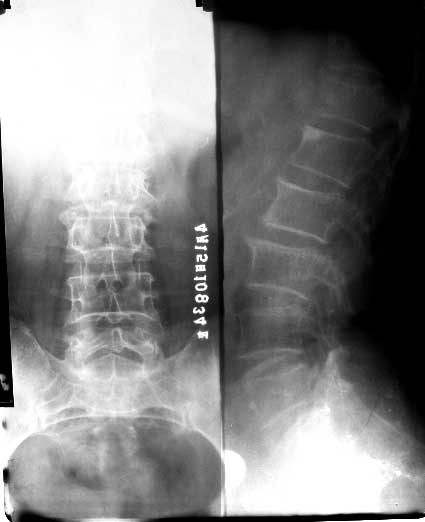

f/43y,腰部痛。

典型椎体致密性骨炎.(l1)

致密性骨炎是一种骨质硬化性疾病.多见于髂骨 腰椎 骶骨和耻骨.

至今病因不详,也就不必再议.  腰椎好发于l前上角,呈三角形影.

椎间隙正常.

l1椎体前上部致密影,为典型的致密性骨炎。此外,该例尚有腰椎骨质增生改变。

腰椎致密性骨炎

图片来源徐爱德主编,骨关节疾病影像学图鉴p197

腰椎好发于l前上角,呈三角形影.